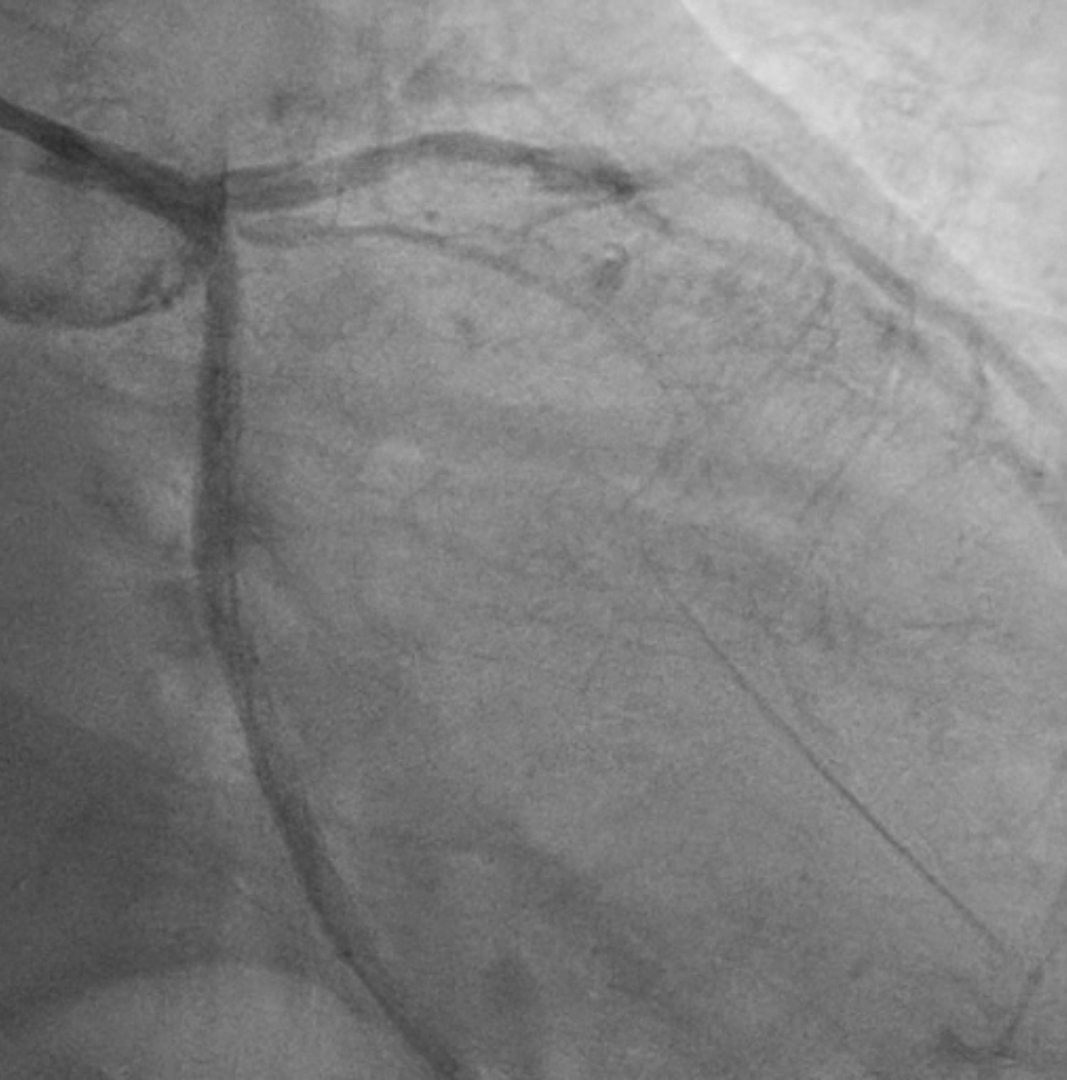

Procedural Step

Two months ago, PCI of the LAD wasattempted. The guidewire successfully crossed to the distal LAD, but a 2.5 mmscoring balloon could not cross the mid lesion and showed a ¡°dog-bone¡±appearance upon inflation, so the procedure was stopped, and PCI of the LCx wasperformed instead. We reattempted PCI of the LAD using a Mach CLS 7 Fr guidingcatheter. A Fielder XT wire crossed to the distal LAD, but the OCT cathetercould not cross the lesion. Lesion preparation with a 2.0 mm scoring balloon athigh pressure and a 2.0 mm Wolverine cutting balloon enabled OCT passage. OCTimaging revealed fibrous and nodular calcification in the mid LAD, with aminimal lumen area of 1.71 mm and reference diameters of 4.0 mm (proximal) and3.3 mm (distal). Orbital atherectomy using a Diamondback 360 (1.25 mm crown)was performed carefully due to vessel tortuosity, with 10 runs at80,000–120,000 rpm. Post-atherectomy OCT showed reduced calcium burden andincreased lumen area. Further lesion preparation with 2.5 and 2.75 mm scoringballoons showed no ¡°dog-bone¡± sign, indicating adequate calcium fracture. A 3.0¡¿ 46 mm Amphilimus DES was implanted in the proximal–mid LAD and post-dilatedwith a 3.5 mm NC balloon. Final angiography showed TIMI 3 flow withoutdissection. Post-stent OCT showed good apposition, MSA 8.84 mm©÷ proximally and5.73 mm©÷ distally, with 99% expansion. The patient remained hemodynamicallystable and was discharged the following day.